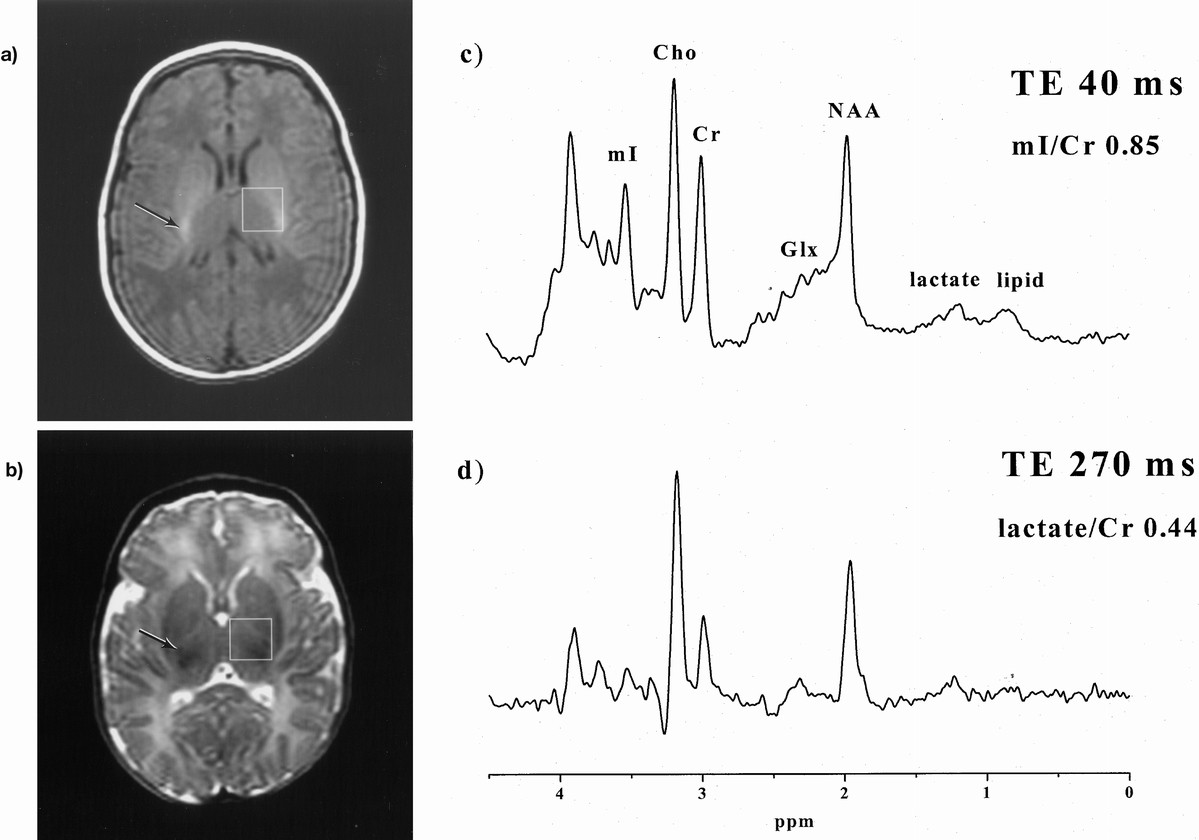

Early Increases In Brain Myo Inositol Measured By Proton Magnetic Resonance Spectroscopy In Term Infants With Neonatal Encephalopathy Pediatric Research